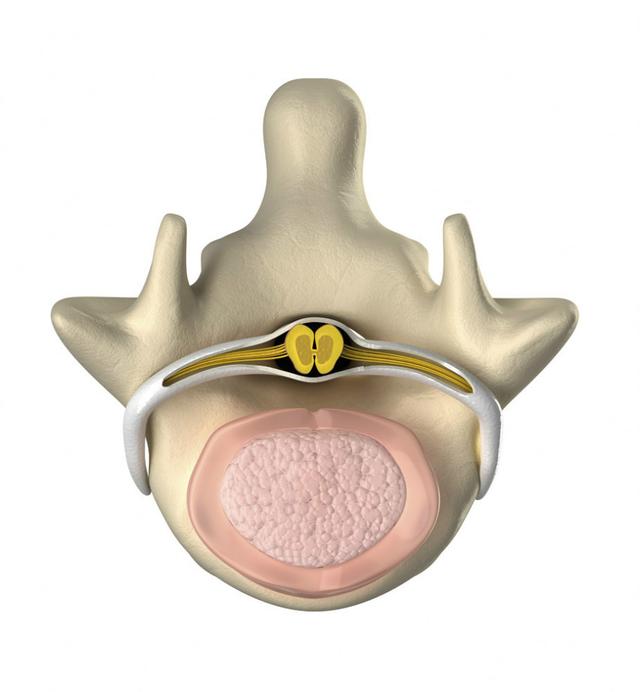

从一方面来说,人类是弱小的,容易生病,容易受伤,但从另一方面来说,人类也是强大的...